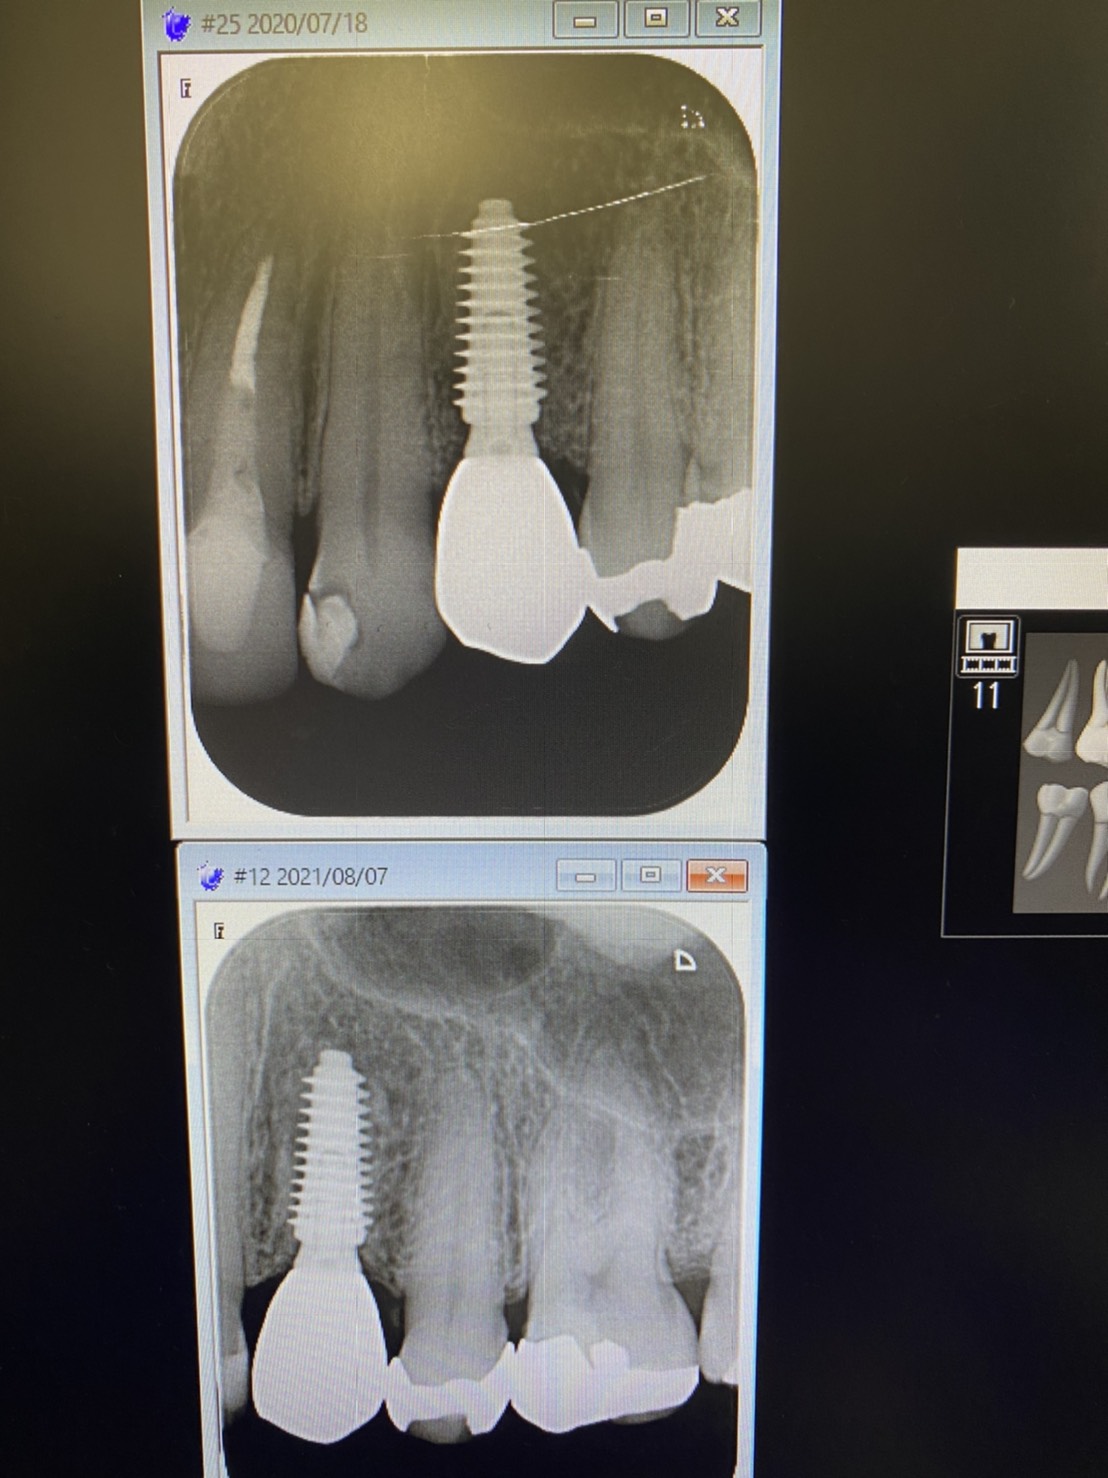

初めは昨年装着した方の定期検診

M.B.Lもなく、プラットフォーム上にも骨梁が緻密化され段々と白線化、皮質骨化してます

グッド!だね